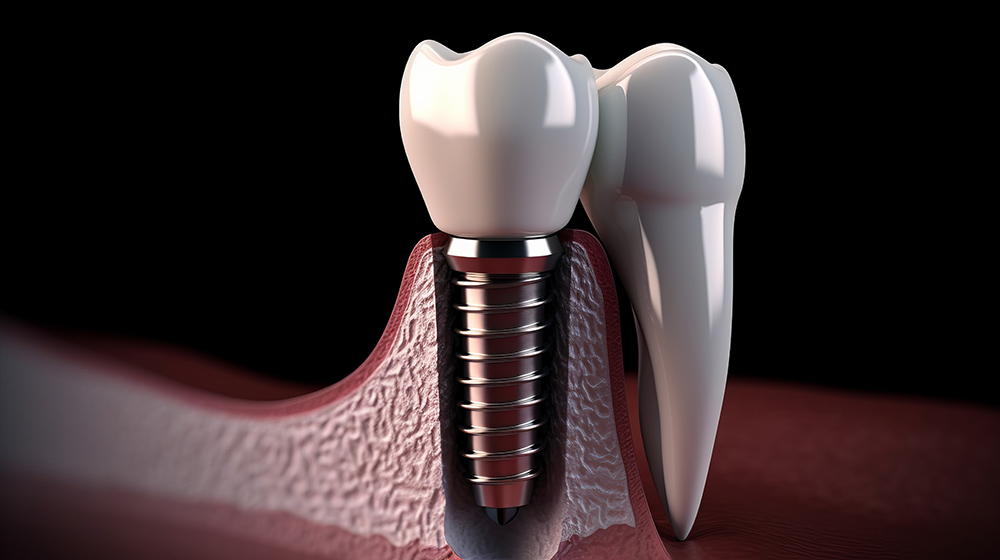

임플란트의 수명은 많은 환자들이 가장 궁금해하는 부분 중 하나입니다. 일반적으로 임플란트는 적절한 관리와 정기적인 치과 검진을 통해 평생 사용할 수 있습니다. 그러나 임플란트의 수명은 여러 요인에 의해 영향을 받을 수 있습니다.

첫째, 환자의 구강 위생 상태가 중요한 역할을 합니다. 정기적인 양치와 치실 사용, 치과 검진을 통해 구강 건강을 유지하면 임플란트의 수명을 연장할 수 있습니다.

둘째, 임플란트의 소재와 품질도 수명에 영향을 미칩니다. 고품질의 임플란트를 사용할수록 오랜 기간 동안 안정적으로 사용할 수 있습니다.

셋째, 시술 후 관리가 중요합니다. 과도한 힘을 가하지 않도록 주의하고, 치과의사의 지시에 따라 주기적인 검진과 관리를 받는 것이 필요합니다.

넷째, 환자의 생활 습관도 임플란트 수명에 영향을 미칠 수 있습니다. 흡연이나 과도한 음주는 임플란트 주위의 뼈와 잇몸 건강을 해칠 수 있으며, 이는 임플란트의 수명을 단축시키는 요인이 될 수 있습니다.